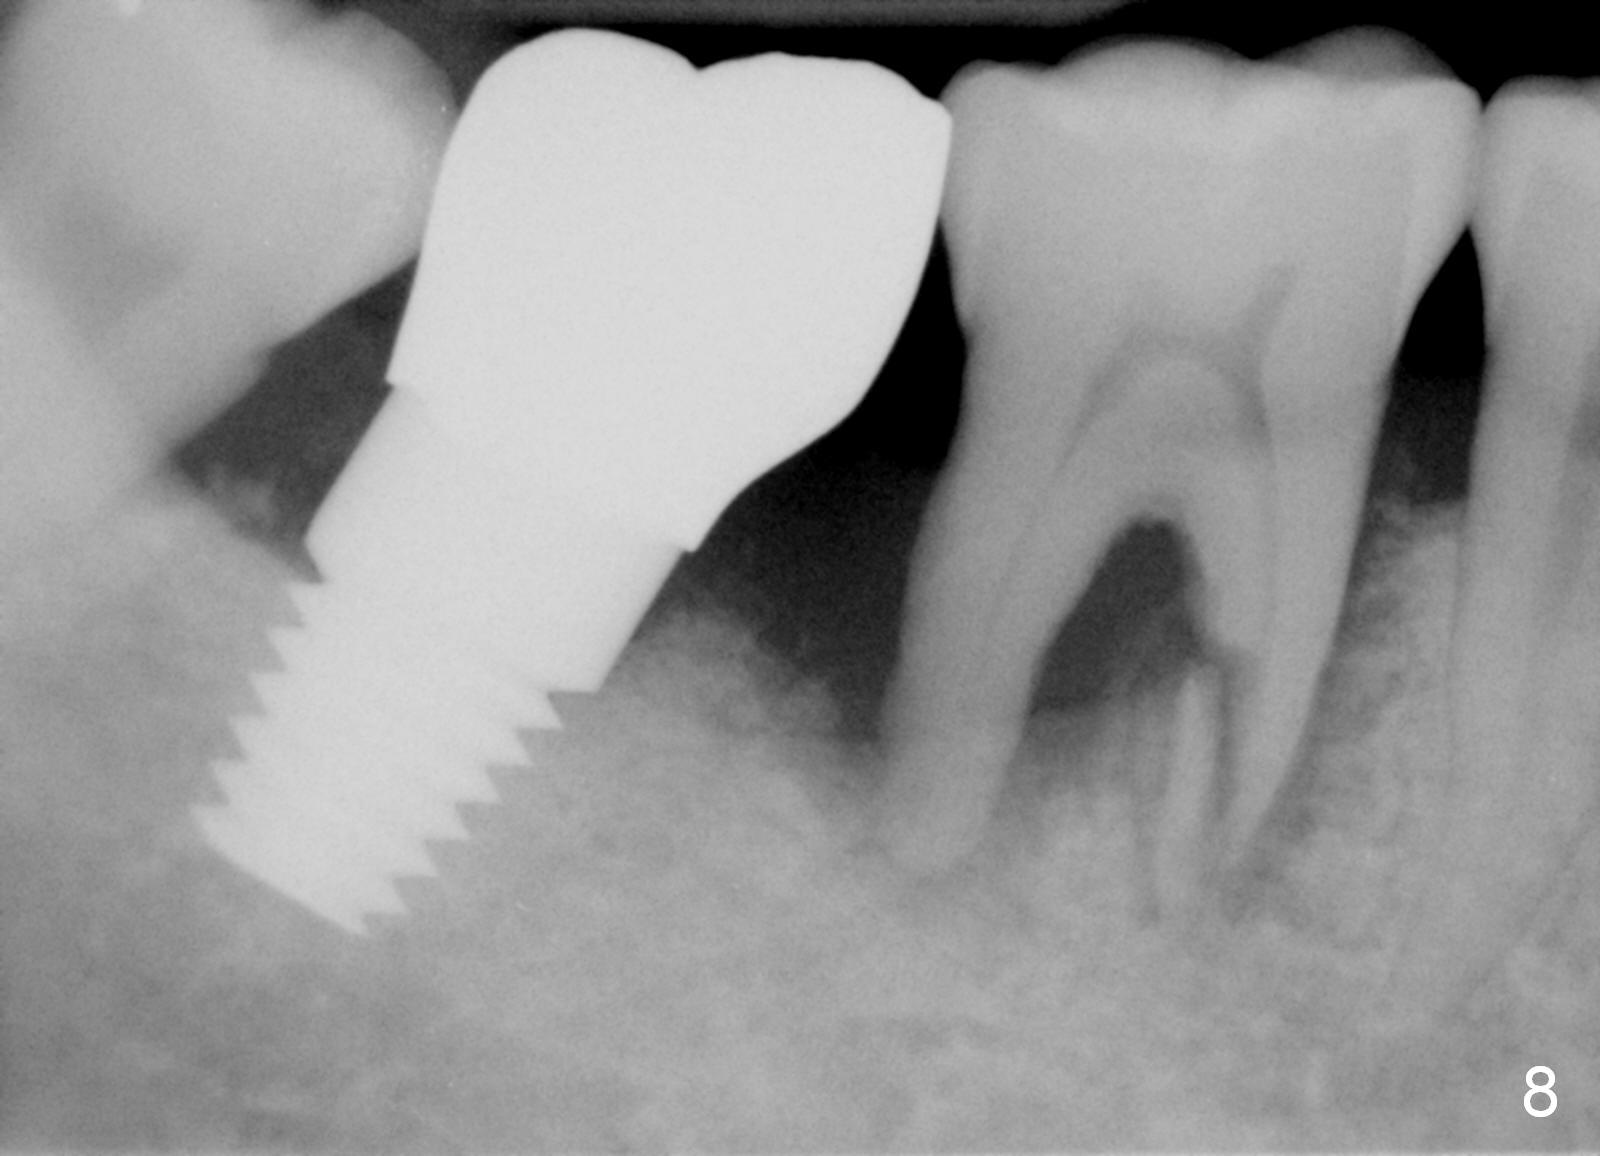

Luckily the patient returns for #31 implantation 4 months post socket preservation. Bone forms in the alveolus and above (Fig.1 black and white arrowheads, respectively). A 6 mm tissue punch is used to open the wound (Fig.2). Osteotomy forms using bone expanders, reamers and taps (Fig.3: 6x14 mm tap). Without infection, local anesthesia is more easily achieved than immediate implant when infection exists. The depth is controlled more readily with delayed implantation. Following adjustment of trajectory, a 7x11 mm implant is placed with insertion torque 60 Ncm (Fig.4 I). Fig.5 shows that the implant obliterates the wound; an abutment (A) is placed to retain perio dressing. With formation of new bone from socket preservation, insertion torque seems to be more easily obtained with the short implant. There is no space to re-use the harvested bone (Fig.6). The implant remains stable postop. Apparent new bone is forming toward the distal coronal threads 5 months postop (Fig.7). The bone around the implant remains stable 17 months post cementation (Fig.8), although there is an episode infection at the neighboring tooth (#30). The patient is more eager to have implants for the maxilla, since the flipper has lost. After implant placement at #7, the pain at #30 becomes more severe.